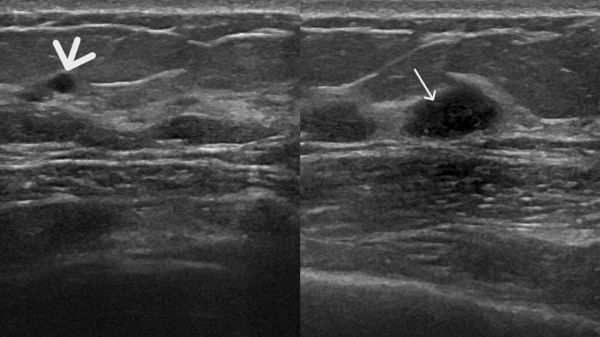

患者B钼靶检出多发钙化灶,超声虽未显示钙化,但发现了钼靶未显示的实性结节(如图3、4)。

图4 患者B的超声图像,显示未见钼靶所示钙化灶,但扫查到乳腺实性低回声结节(图中箭头处)